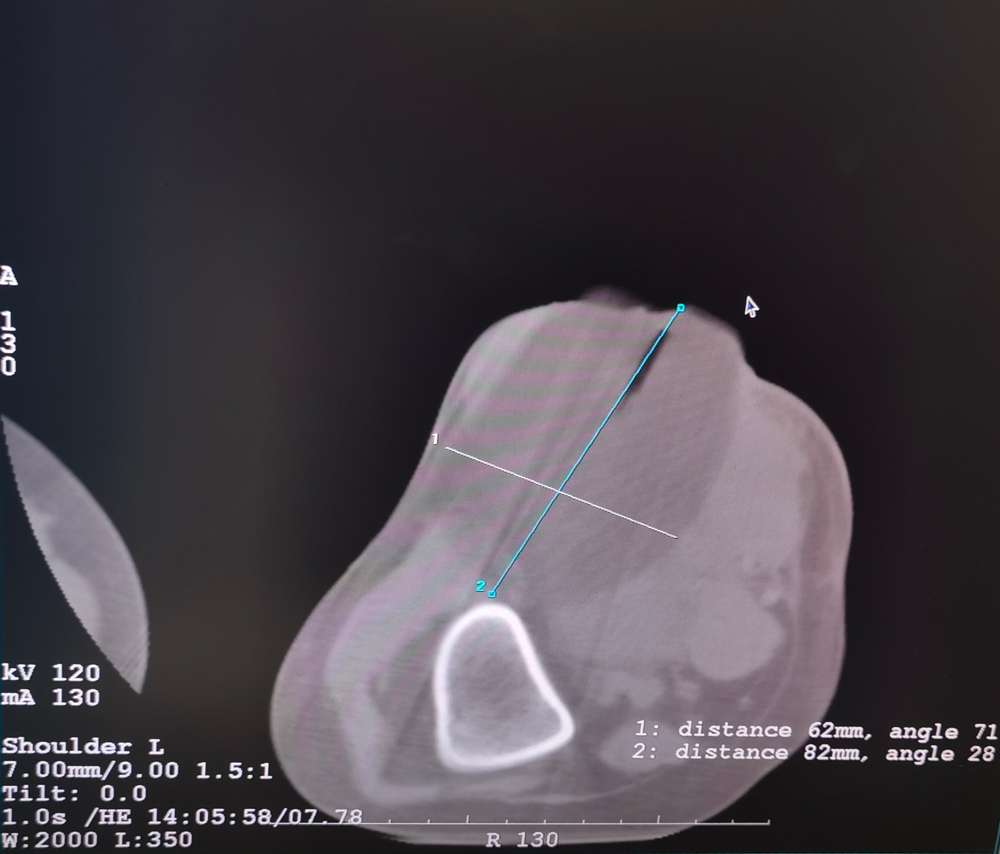

女,42歲,復發性脂肪瘤,病灶位于右側膝關節,直徑大小13cm。采用雙針方案,共進行6個凍融循環,最大冰球直徑達8.2cm,術中多方位治療全面覆蓋病灶范圍。患者術后狀況良好。